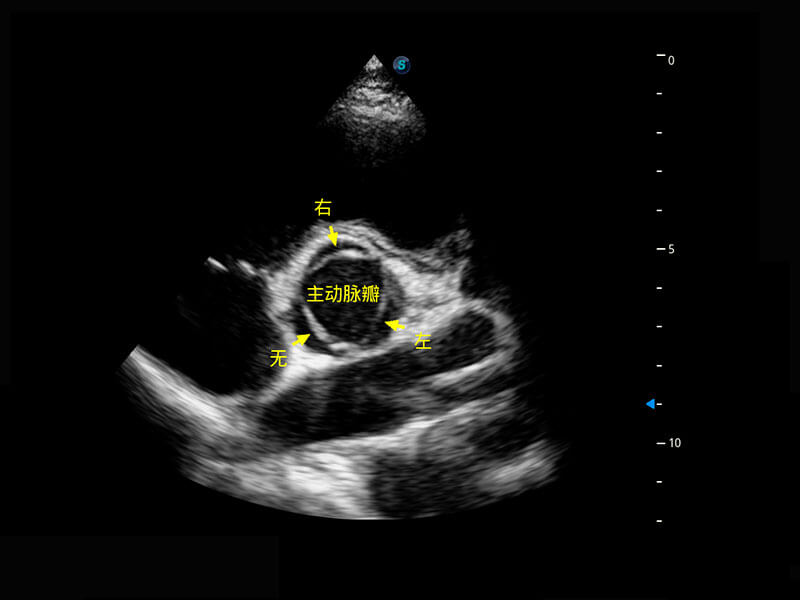

P60搭載一系列胎兒心臟成像技術(shù),實(shí)現(xiàn)精細(xì)的胎兒心臟評(píng)估。

四腔切面

四腔心血流

右室雙出口

胎心容積成像